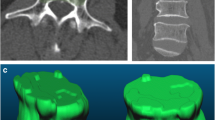

This retrospective study included patients within 6 weeks of back pain (non-traumatic) who underwent MRI and were diagnosed with benign and malignant indistinguishable VCFs. The two cohorts were retrospectively recruited from the Affiliated Hospital of Qingdao University (QUH) and Qinghai Red Cross Hospital (QRCH). Three hundred seventy-six participants from QUH were divided into the training (n = 263) and validation (n = 113) cohort based on the date of MRI examination. One hundred three participants from QRCH were used to evaluate the external generalizability of our prediction models. A total of 1045 radiomic features were extracted from each region of interest (ROI) and used to establish the models. The prediction models were established based on 7 different classifiers.